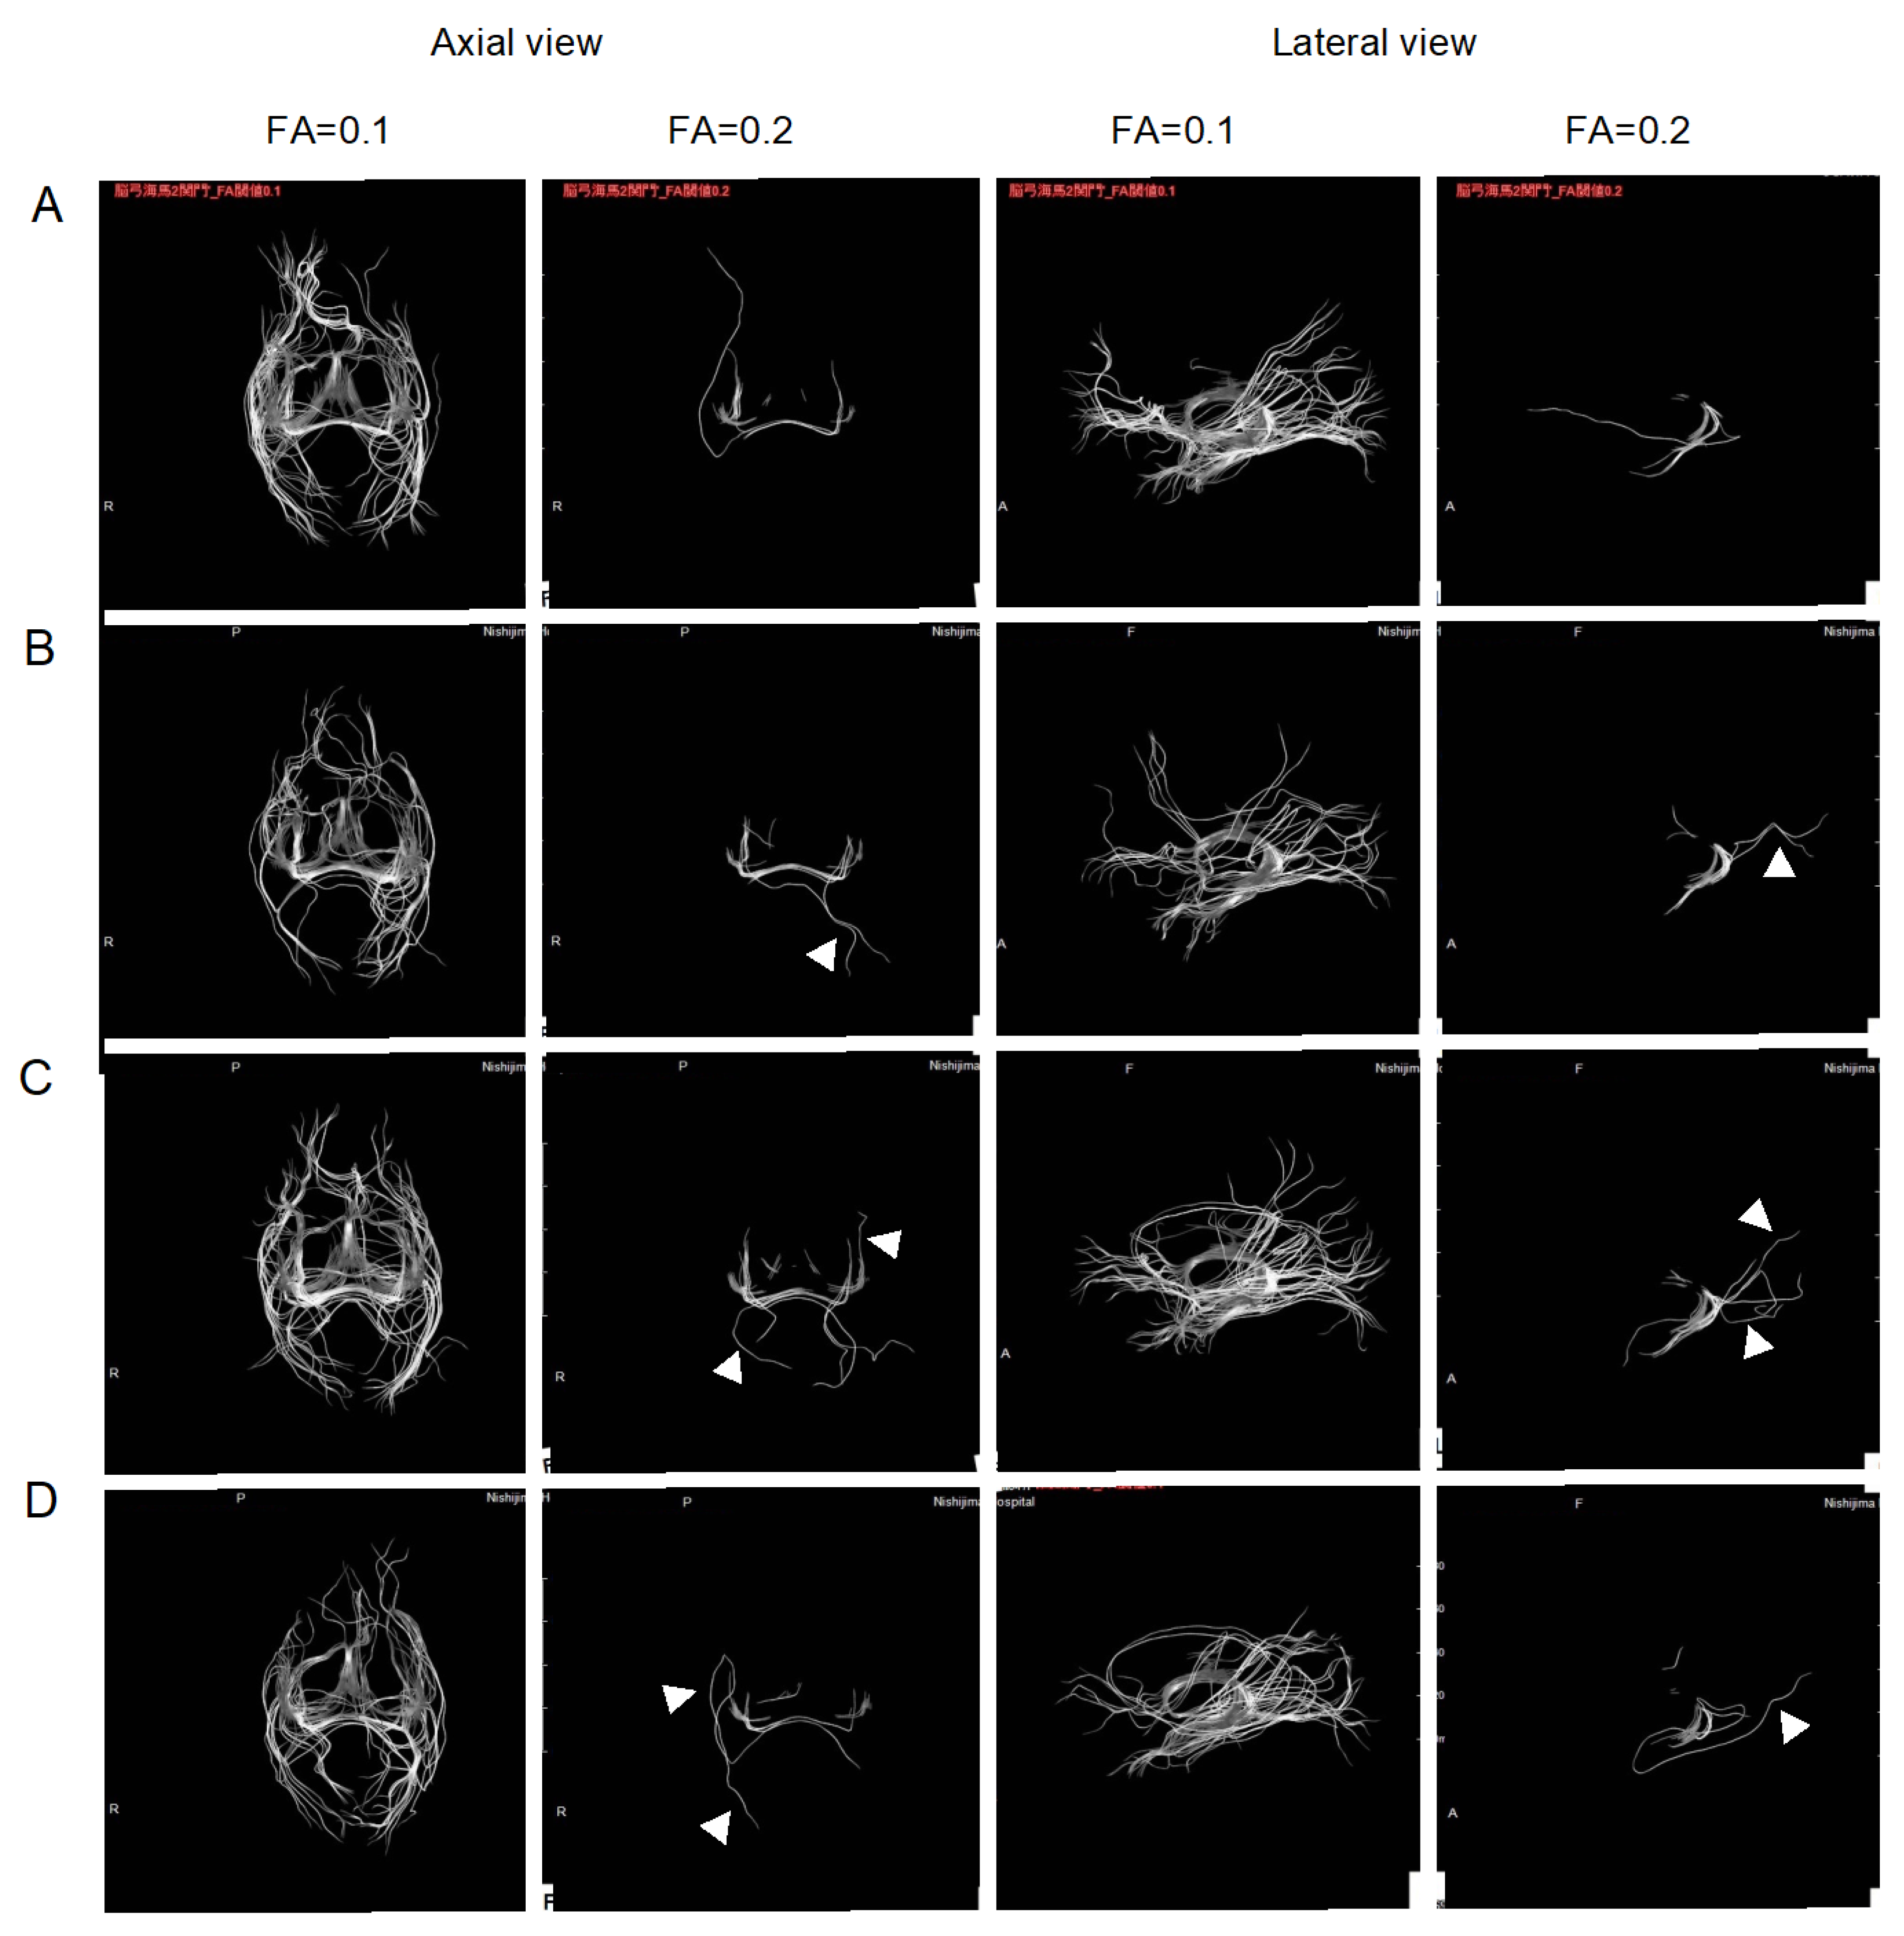

2.2. Improvement of Neurons by H2 Inhalation as Assessed by Diffusion Tensor Imaging

4.6. Measurement of the Integrity of Neurons by Diffusion Tensor Imaging